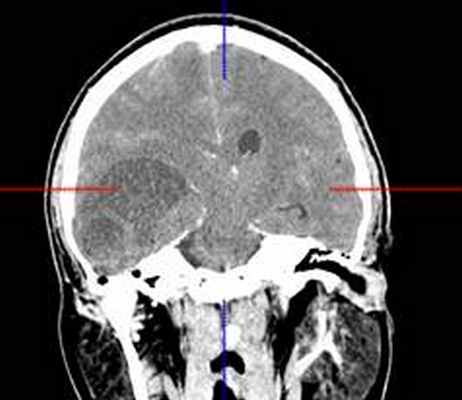

КТ головного мозга с контрастным усилением (24.03.2015): объемное кистозно-солидное образование правой теменно-височно-лобной области. Дислокационный синдром.

22.10.2015 была выполнена операция: микрохирургическое удаление опухоли правой височной доли под интраоперационными навигационным контролем и с интраоперационной фотодинамической терапией.

КТ головного мозга (23.10.2015): не выявило признаков кровоизлияния или каких-либо других хирургических осложнений в области оперативного вмешательства.